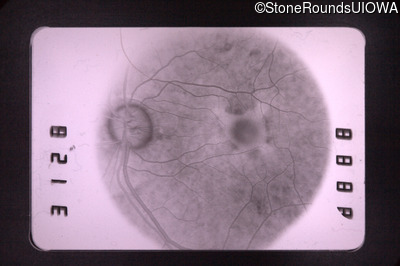

Fluorescein Angiography - Right - 20/50 +1

Exemplar